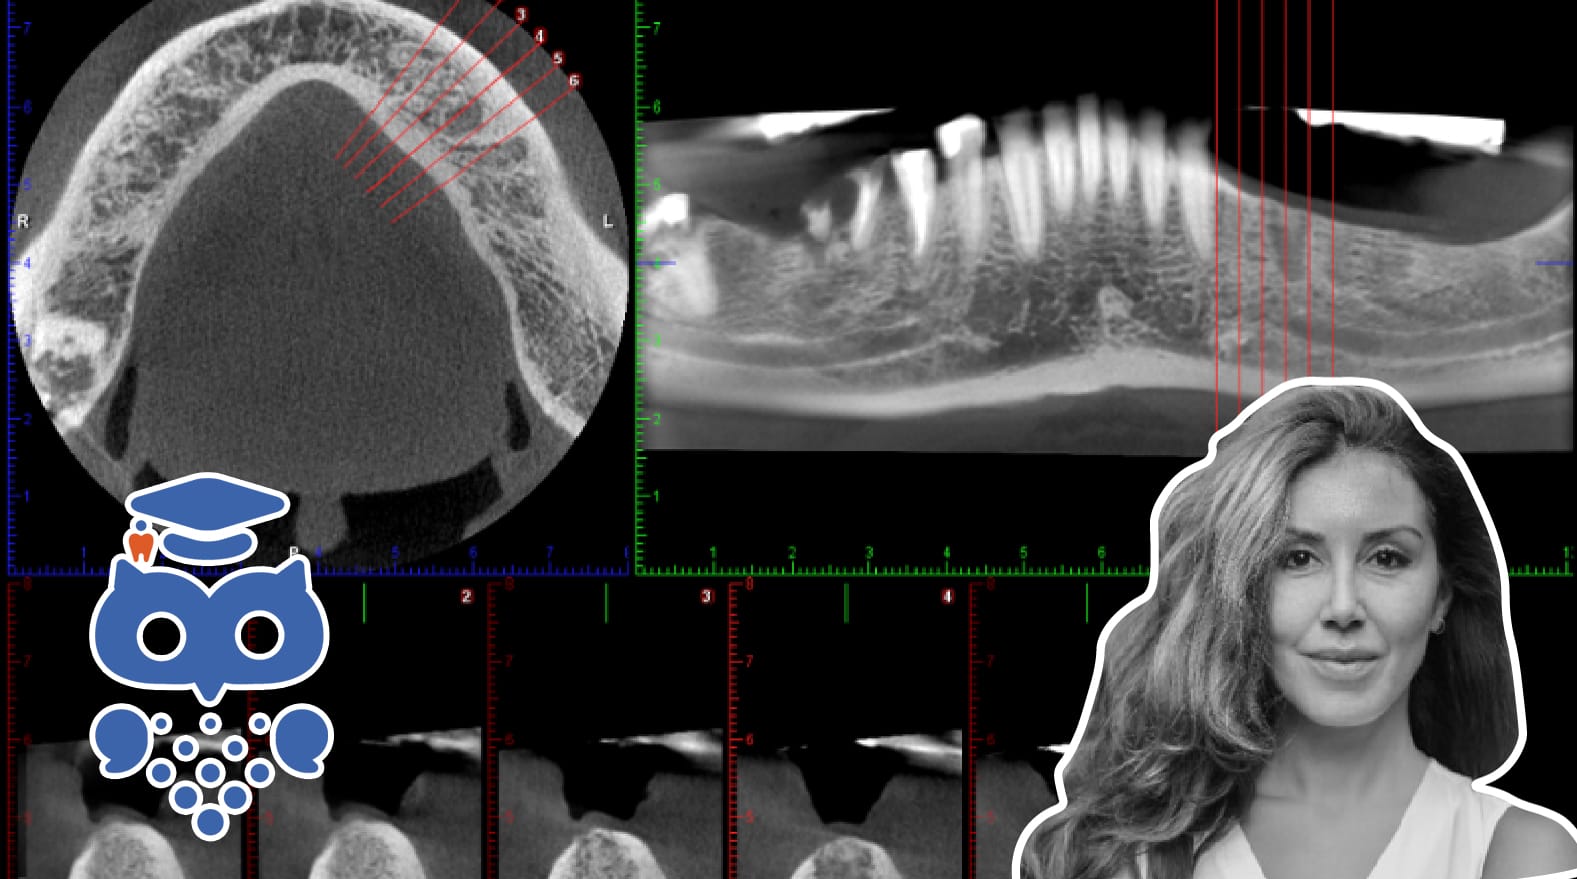

I samband med rotationen skapas ett stort antal projektioner och ur dessa framställs en digital volym från vilken bilder rekonstrueras i tre mot varandra vinkelräta plan; axiala, coronala (frontala) och sagittala (Figur 2).

Projektionsgeometrin och principerna för avbildning av en volym skiljer sig mot konventionell datortomografi (CT) där istället enstaka tunna snitt, vanligen i axialplan, avbildas med hjälp av smalt, solfjäderformat strålknippe och där de enstaka snitten sedan sammanfogas för att bilda volymsdata (Figur 3).